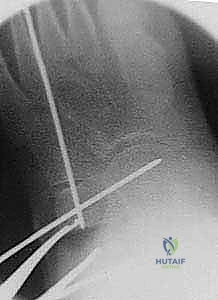

5. التثبيت الداخلي (Internal Fixation)

لضمان عدم تحرك الطعم العظمي أثناء فترة الالتئام، يتم تثبيت التكوين الجديد. يستخدم الدكتور هطيف أحدث تقنيات التثبيت، والتي قد تشمل شريحة معدنية صغيرة مع مسامير (Plate and Screws)، أو مسامير معدنية تمر عبر العظم، أو أسلاك كيرشنر (K-wires)، وذلك لضمان أقصى درجات الثبات الميكانيكي.

يتم التأكد من صحة التثبيت والتصحيح باستخدام جهاز الأشعة السينية المباشر (C-arm Fluoroscopy) داخل غرفة العمليات قبل إغلاق الجرح.